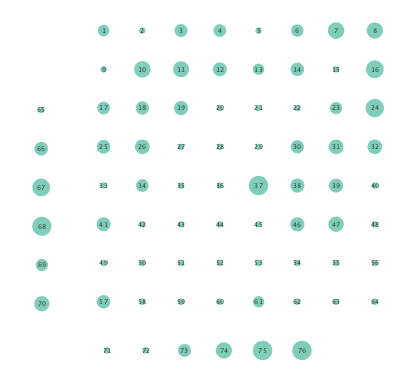

Finally, Figure 6 depicts the closeness centrality computed per node in the inferred networks. Closeness centrality measures how reachable a node is from all other nodes, and is generally defined as the reciprocal of the sum of geodesic distances of the node from all other nodes in the network; see also [24]. Once again, Figure 6 depicts a more general decrease in closeness centralities after seizure onset in networks inferred by the nonlinear SVARM, as compared to the linear variant. This empirical result indicates a change in reachability between regions of the brain during an epileptic seizure.

Moreover, the performance of K-SVARM with data-driven kernel selection was also tested. Figure 7 illustrates the per node degree as well as the closeness centrality of networks inferred from preictal and ictal phases. Consistent with Figures 3 and 6, Figure 7 again reveals universal decrease in node degrees as well as closeness centrality at seizure onset.